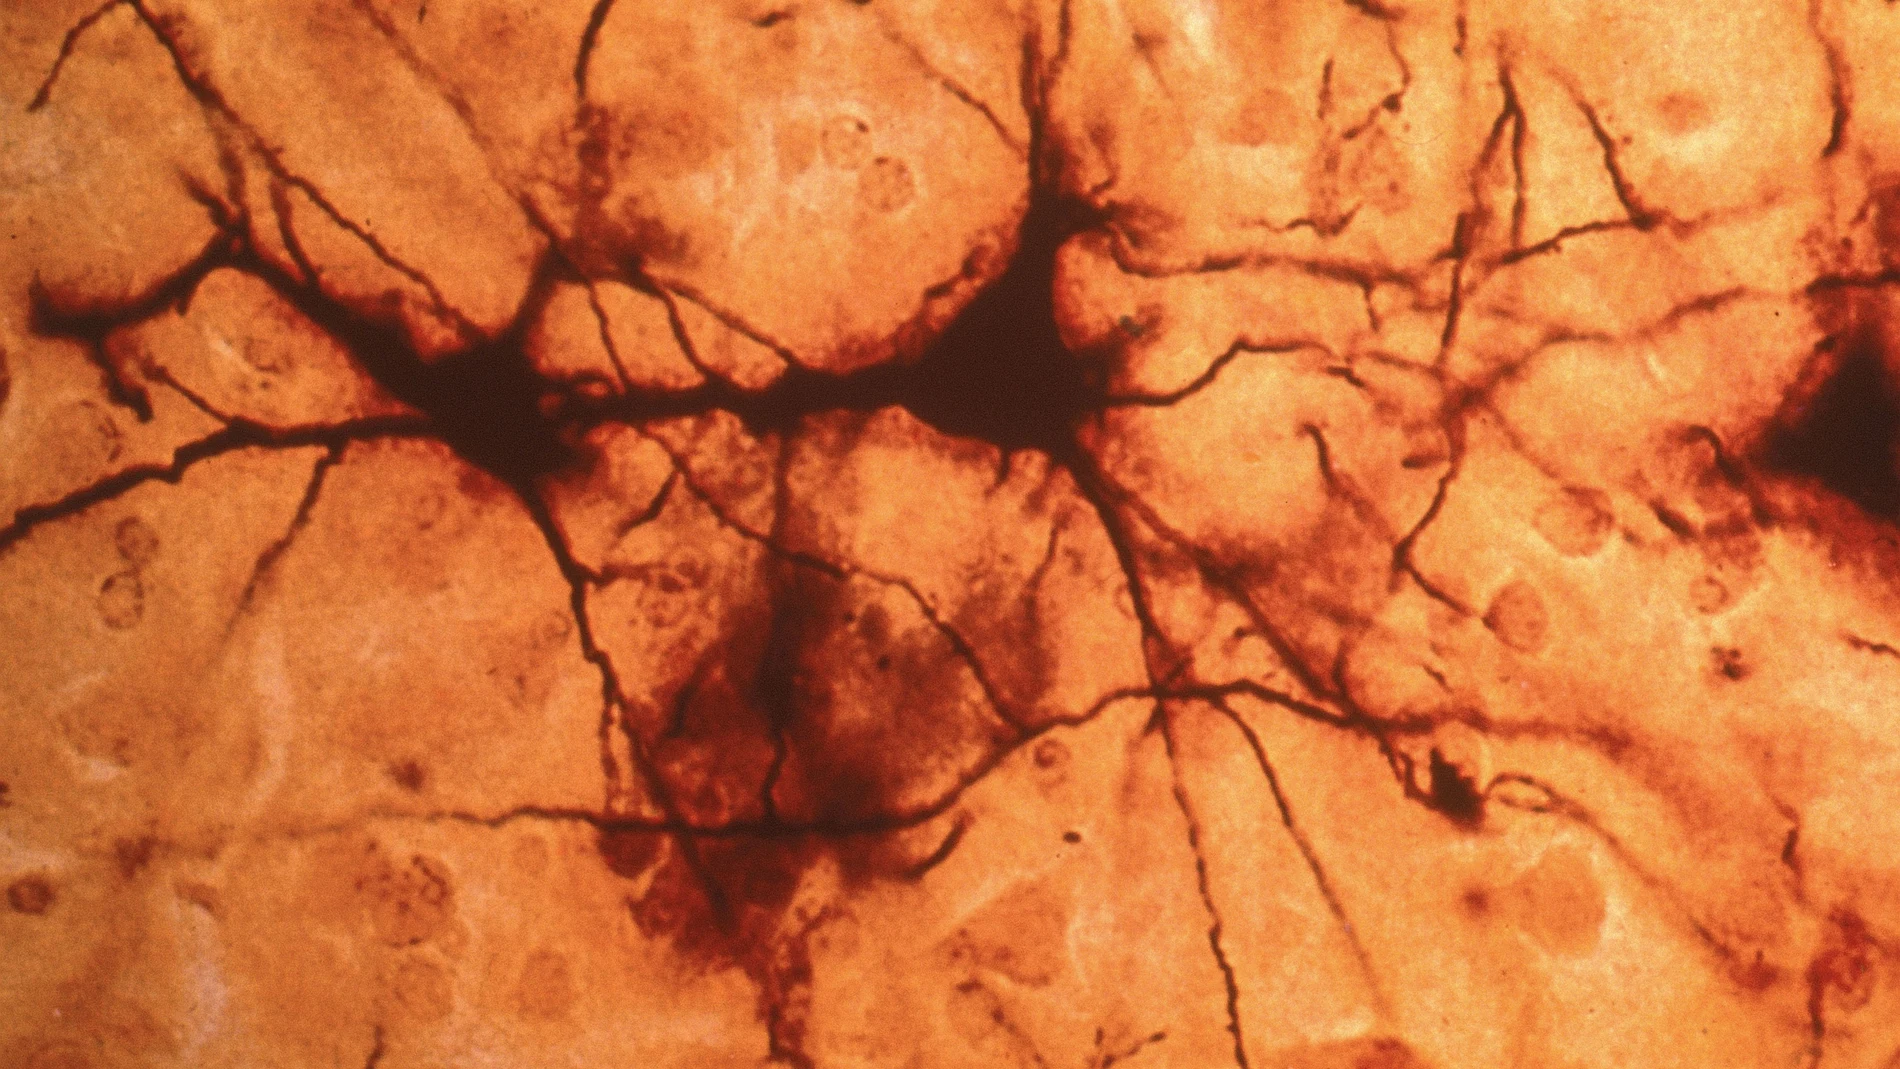

El Instituto de Neurociencias (IN), centro mixto del Consejo Superior de Investigaciones Científicas (CSIC) y la Universidad Miguel Hernández (UMH) de Elche, han realizado un estudio con el que han descubierto que un grupo de neuronas de la amígdala, la zona del cerebro que regula las emociones, juega un papel fundamental en la aparición de alteraciones como la ansiedad, la depresión y los cambios en la conducta social.

Los investigadores trabajaron con ratones modificados genéticamente para que expresaran en exceso un receptor cerebral llamado GluK4, que se activa con el glutamato. Esta modificación hace que aumente la fuerza con la que las neuronas se comunican.